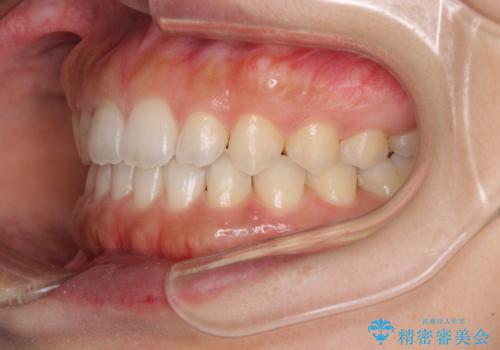

気になる隙間の再矯正 前歯をインビザライン・ライトで改善

- 後戻りによる上下前歯の隙間を気にして来院された患者様です。

歯列不正はそれほど大きくなかったため、インビザライン・ライトを用いて矯正治療を行うこととしました。

無理のないペースで治療を進め、9ヶ月で終えることができました。